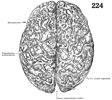

上大脳静脈【じょうだいのうじょうみゃく】 Superior veins of the cerebral cortex that open into the superior sagittal sinus from the lateral medial, and anterior inferior surface of the cerebrum.(上大脳静脈は大脳半球の外側の凸面および内側面からの血液を集めて、上矢状静脈洞に入る。この静脈は10~15本あって(流出する領域によって前頭前野静脈、前頭静脈、頭頂静脈、側頭静脈、後頭静脈の5群に分けられる)、斜め前方に走り上矢状静脈洞に入る。したがって上大脳静脈が静脈洞に入る血流方向は、静脈洞内の血流とは反対の方向に注ぐことになる。大脳半球の内側面から来る静脈の一部は下矢状静脈洞にも入る。)